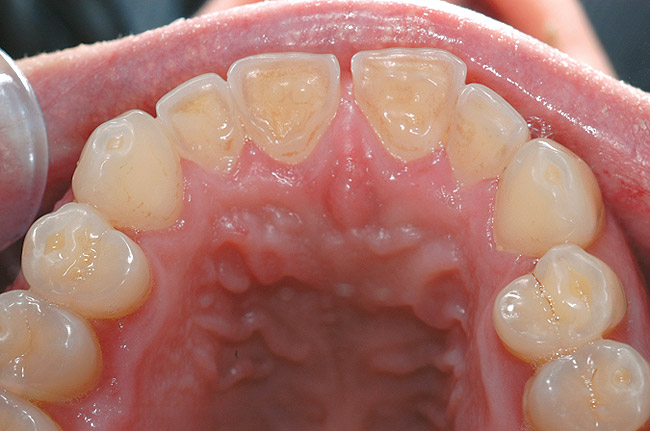

Figure 2  The erosion on the palatal surfaces of the upper incisors was more advanced than on the bicuspids, which show earlier signs of erosion. The cause could not be attrition, so the most likely explanation was erosion. The typical hollowed-out occlusal surfaces on the teeth are indicative of erosion.

Figure 2

The first signs of tooth wear may not be immediately recognizable because changes to the enamel surface can be difficult to diagnose. The mamelons on the incisal edge of incisors wear away within the first decade after eruption, but other less obvious changes also occur (Figure 1). The cusp tips of molars and premolars may flatten as may the facial surfaces of upper incisors. If allowed to progress, eventually the enamel is worn away, exposing small areas of dentin (Figure 2). Dentin exposure is much easier for dentists to recognize, but it means that considerable amounts of the tooth have been lost. Ideally, therefore, early diagnosis should help to prevent the lesion from progressing into dentin. If the process of tooth wear continues without intervention, almost total destruction of the tooth can occur (Figure 3).